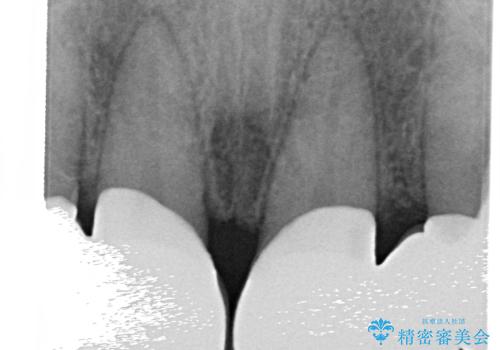

- 前歯部のすきっぱと歯並びが気になるので診て欲しいといらっしゃった方の症例です。

全顎矯正は御希望されなかったため、上顎前歯部のみの部分矯正とオールセラミッククラウンによる補綴を行いました。